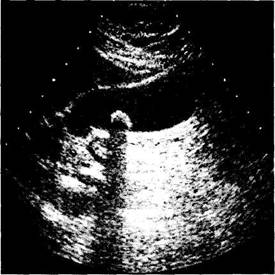

c) Ecografia hepatica este un procedeu neinvaziv care se foloseste ca metoda de triaj si care aduce informatii despre modificarile de dimensiuni si structura hepatica ce apar in unele boli cronice (hepatite cronice, ciroze), identifica prezenta tumorilor solide sau chistice, deceleaza prezenta ascitei, etc.

Fig. 3. Ecografie = litiaza veziculara